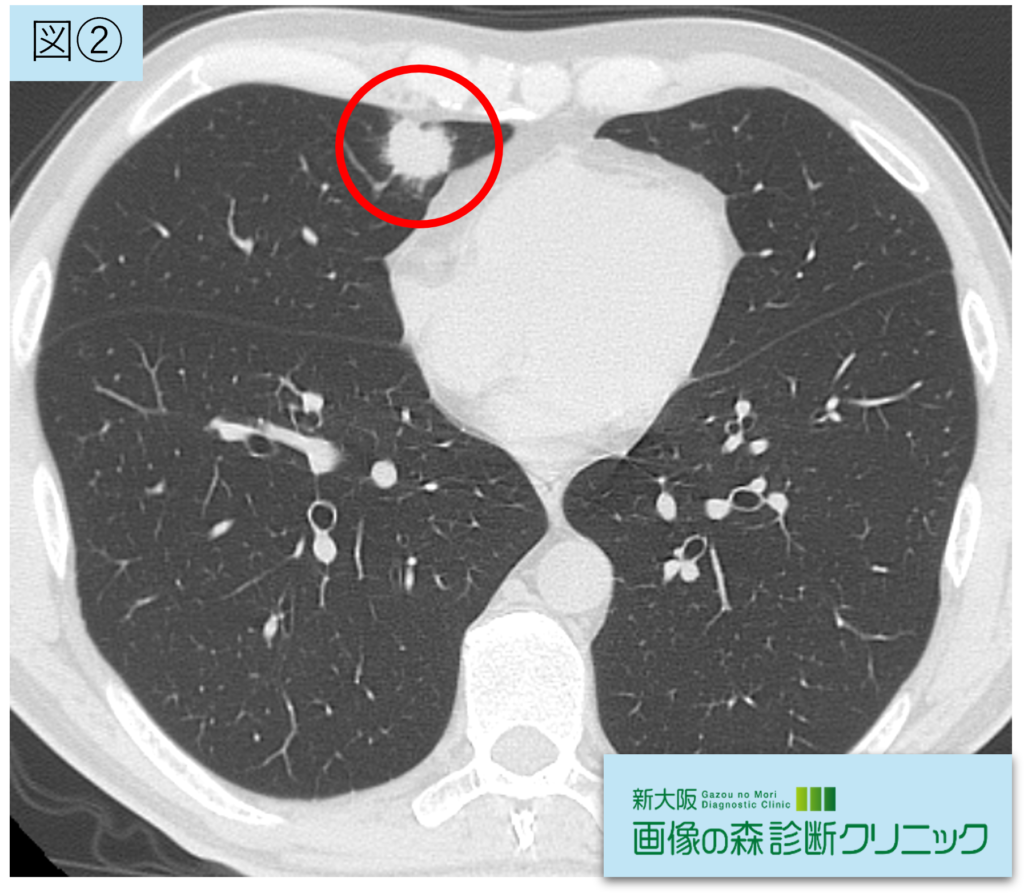

腫瘍画像(横断像)

図②③④:腫瘍画像(赤〇が腫瘍部位です)

右肺中葉に21.5mmの腫瘍性陰影を認めます。辺縁不整(スピクラ)の充実性腫瘤を認め、悪性を疑う所見です。